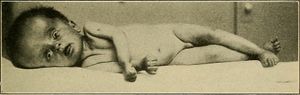

| استسقاء المخ كما يظهر في الأشعة المقطعية على المخ. المناطق السوداء في منتصف المخ هي تضخم غير طبيعي ومملوء بالسوائل. | |